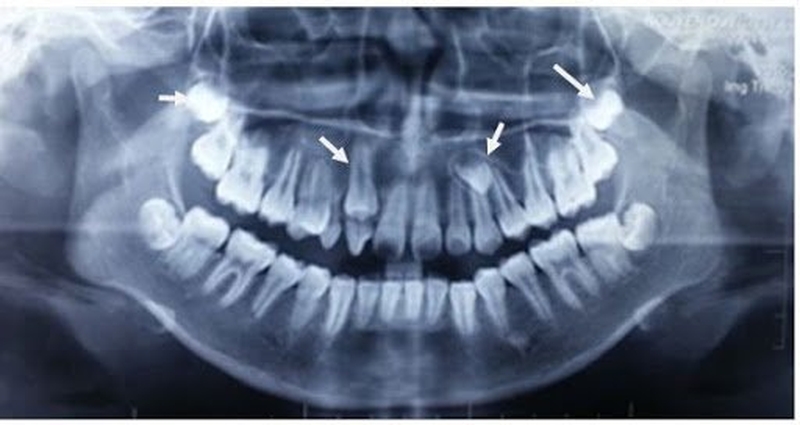

Để tình trạng răng mọc ngầm được chẩn đoán chính xác, trước tiên người bệnh cần tiến hành chụp X quang để phân tích cụ thể. Bên cạnh đó, răng mọc ngầm cũng có thể nhận biết dựa vào một số dấu hiệu răng mọc ngầm lâm sàng như sau:

• Răng ngầm thường xuất hiện muộn.

• Khi chạm vào vùng xương ổ răng thấy có vùng lợi trồi lên một cách bất thường.

• Nướu sưng đỏ giống như dấu hiệu mọc răng nhưng lại không thấy có răng trồi lên.

• Răng mọc ngầm có thể làm đau hay cảm giác ê buốt khi ăn nhai.

• Hôi miệng hoặc thấy đắng ở miệng do phần nướu bị sưng có thể khiến cho các mảnh vụn thức ăn mắc kẹt lại và trở thành nơi trú ngụ lý tưởng cho vi khuẩn. Từ đó điều này gây ra các triệu chứng hôi miệng cũng như hơi thở có mùi hôi khó chịu.